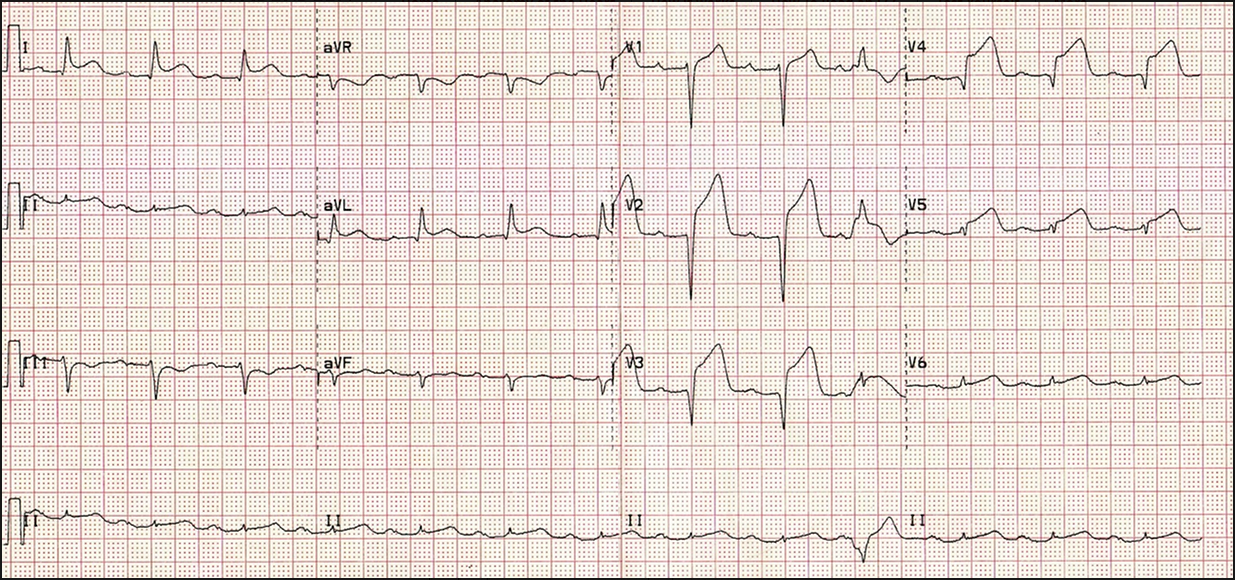

Anterior MI:

This happens due to occlusion of the left anterior descending coronary artery

Look at the chest leads V1-6. There is elevation in the ST segment for each of these.

This suggests that the MI has occurred in the anterolateral segment of the heart since the anterior leads V3 and 4 as well as the lateral leads V5 and 6 have the most marked elevation.

NOTE: there is also reciprocal ST depression in the inferior leads, mainly III and aVF